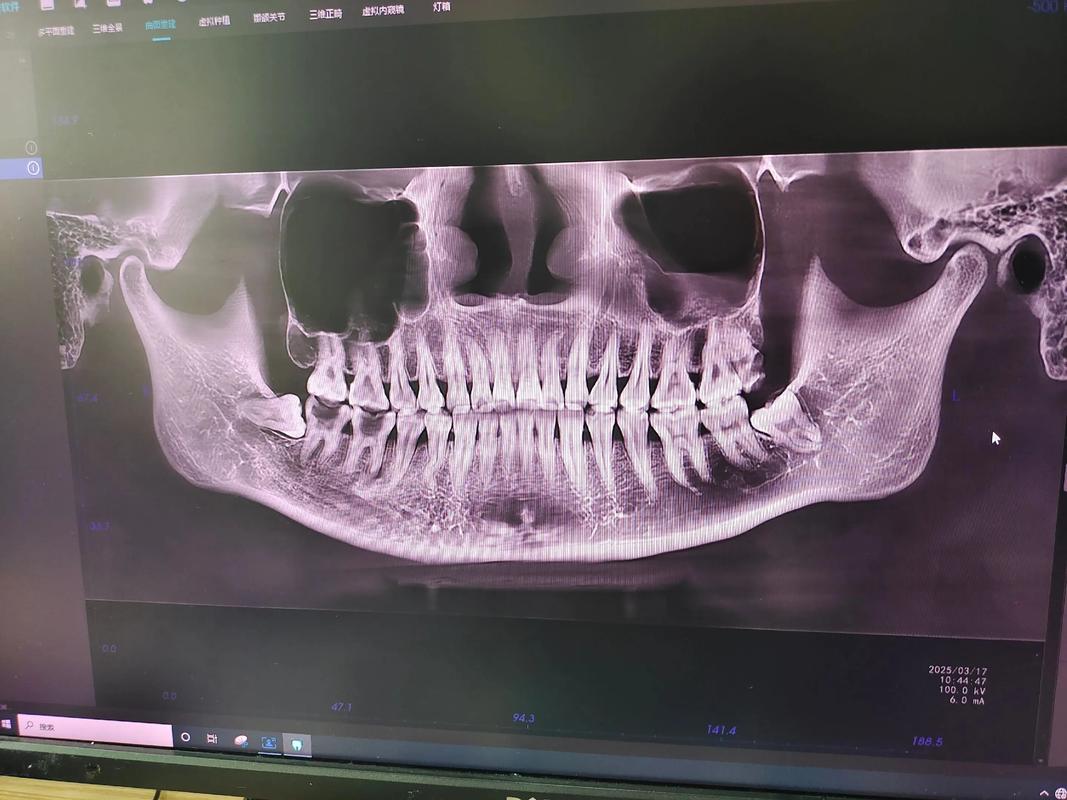

在传统正畸影像中,全景片(曲面断层片)和头颅侧位片是最常用的两种影像,其平行线规范各有侧重,但核心均围绕“解剖基准与定位平面的平行”展开。

全景片的平行线定位:全景片主要用于观察全口牙列的形态、牙根位置、牙槽骨状况及埋伏牙位置,拍摄时,需确保患者的矢状面(通过鼻尖、颏部中点的正中平面)与定位板的矢状标志线严格平行,同时眶耳平面与地面垂直(或与设备设定的水平面平行),这一平行关系可避免牙列在影像中的左右重叠或放大率差异,若矢状面偏斜,可能导致对侧牙齿影像重叠,影响对牙根弯曲、吸收的判断;而眶耳平面倾斜则会导致后牙区影像放大或缩小,干扰对牙冠牙根比例的评估,在全景片的测量分析中,常以“牙长轴平行线”作为参考,通过测量牙长轴与眶耳平面、腭平面(由上颌中切牙尖与第一磨牙近中牙尖构成的平面)的夹角,评估牙齿的倾斜程度,这一测量的准确性依赖于拍摄时定位平面的平行规范。